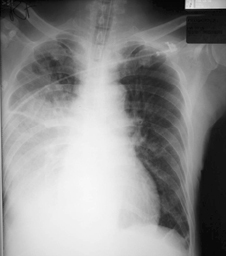

CXR (Fig.3) showed increased right sided consolidation and potent intravenous antibiotic was started.